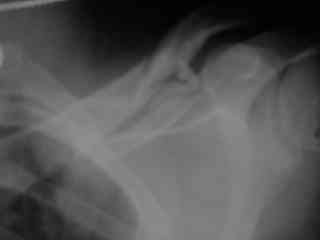

Bolnogo operirovali plastinami, snimky zdes'.

CIMG1145.JPG

Похоже, все прошло по плану. Поздравляю с успешной операцией!